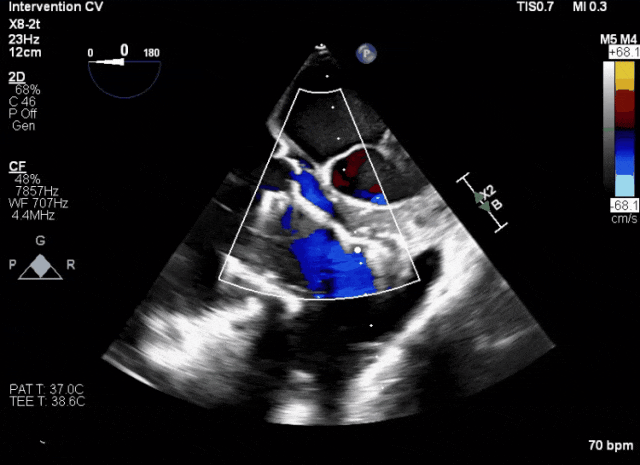

術(shù)后超聲顯示人工瓣膜穩(wěn)定性良好,瓣葉啟閉正常

第二例患者手術(shù)難點

1、患者左心機械瓣術(shù)后,術(shù)中TEE成像有偽影干擾;2、三尖瓣重度反流,右心房、心室嚴(yán)重擴張致三尖瓣葉拴系,Gap:15.3mm,注意阻擋件抓取瓣葉操作。

術(shù)前超聲顯示三尖瓣重度反流合并拴系

術(shù)中TEE成像困難,偽影干擾